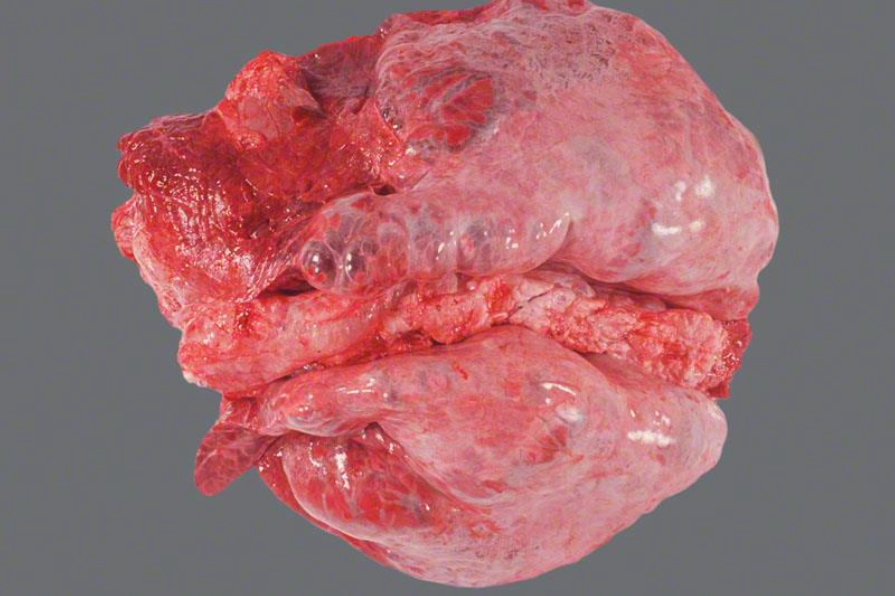

Schwein, Herz: Hochgradige, diffuse, subakute fibrinöse und fibroblastische Peri- und Epikarditis

Herz mit seröser Atrophie

- fibrinöse Epicarditis

- fibrosierende Pericarditis

Gehört zu der angeschnittenen Lunge dazu

Schwein, Lunge: hochgradige, akute bis subakute, multifokale, fibrinöse Pleuropneumonie

- zufällige Verteilung der der Parenchym- und Pleuraveränderungen:

- in Spitzen- und Hauptlappen finden sich multiple landkartenähnliche Herde von roter bis dunkelroter Farbe und verfestigter Konsistenz

- multifokale, gelblichgraue Beläge auf der Pleura (= Fibrin), welche überwiegend mit den Herden des Parenchyms assoziiert sind

- Interstitien teilweise verbreitert